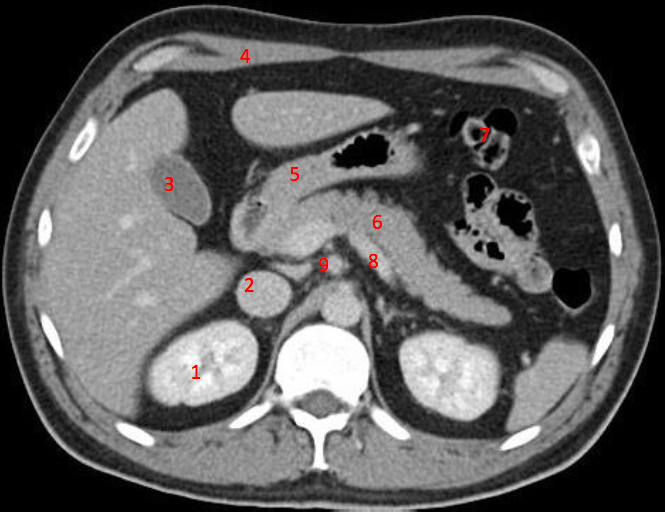

Number 3?

Gall bladder

Number 2?

Rt lobe of liver

Number 10?

Rt rib

Number 4?

Head of pancreas

Number 6?

Stomach

Descending colon

Number 9?

Superior mesenteric artery